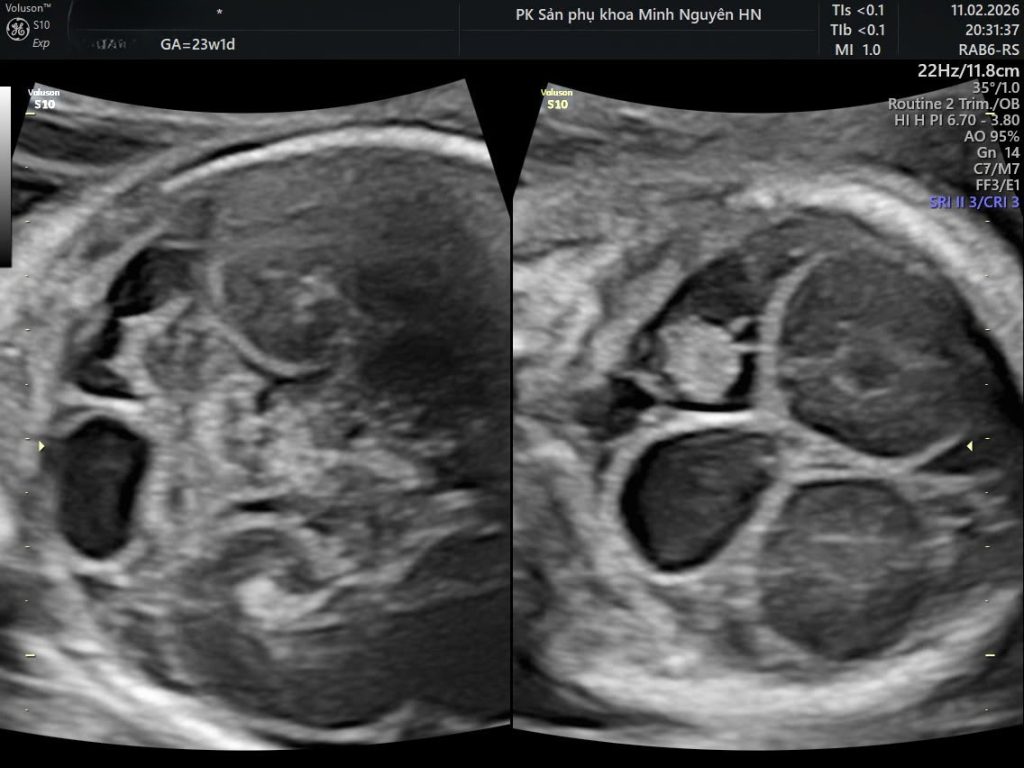

Hình ảnh siêu âm nang màng nhện hố sau

Trên siêu âm hình thái, nang màng nhện hố sau biểu hiện là một khoang trống âm chứa dịch phía sau tiểu não.

Điểm quan trọng nhất là xác định xem khoang dịch đó có thông thương với não thất IV hay không.

Nếu không thông thương, nghĩ nhiều đến nang màng nhện.

• Là túi dịch riêng biệt

• Không thông thương với não thất IV

• Có thể gây chèn ép nhưng không gây thiểu sản